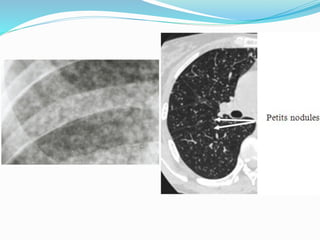

MILIAIRE TUBERCULEUSE

 Dissémination hématogène du BK.

 Observé en cas de TB primaire ou TB post-primaire.

 Aspect miliaire sont sous forme des micronodules

multiples (0,5 à 2mm de diamètre) disséminés dans

les poumons.

 Si les micronodules ne sont pas nombreux, la

radiographie thoracique est normale.

 NB: la visibilité de ces micronodules est la

conséquence de la superposition de certaines

granulomes, les uns sur les autres.